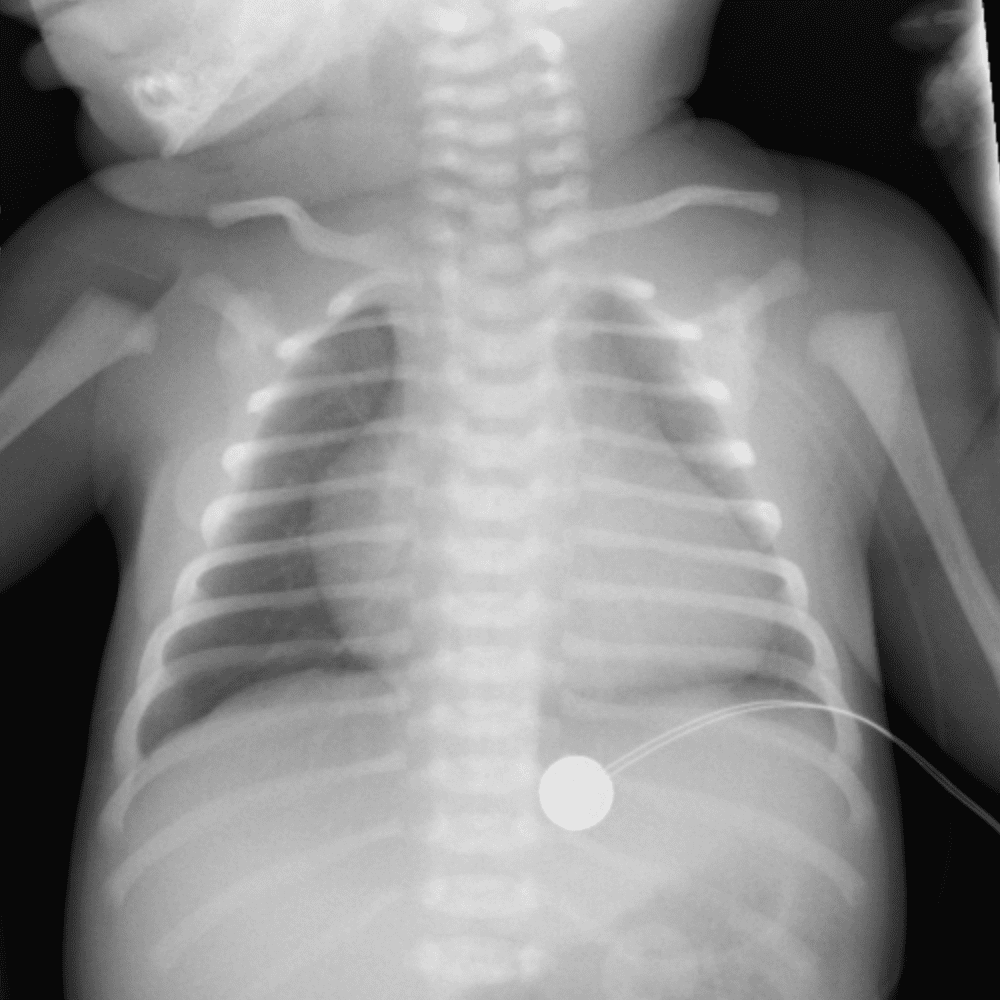

Peds Chest

Practice

Simulates call by including subtle or difficult cases and some normals.

50 cases